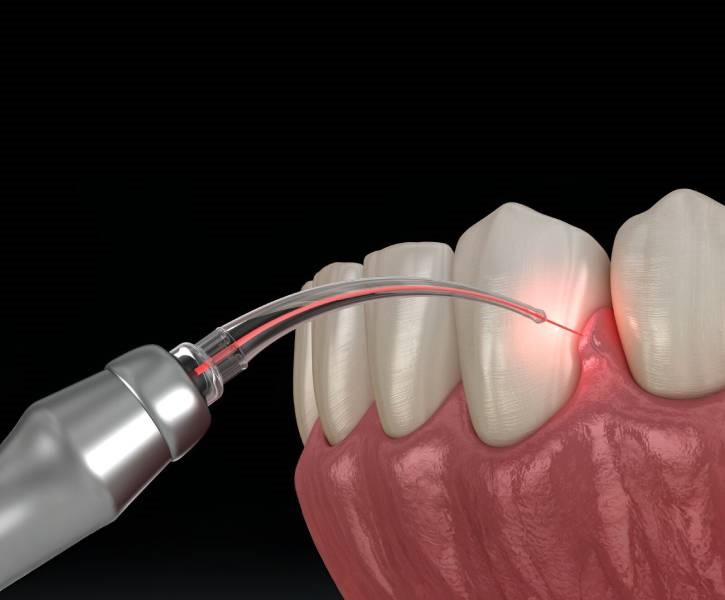

Laser Gum Surgery

Laser gum surgery is a minimally invasive procedure that uses advanced laser technology to treat gum disease and reshape gum tissue. This cutting-edge method ensures precision, faster recovery, and enhanced comfort for patients.